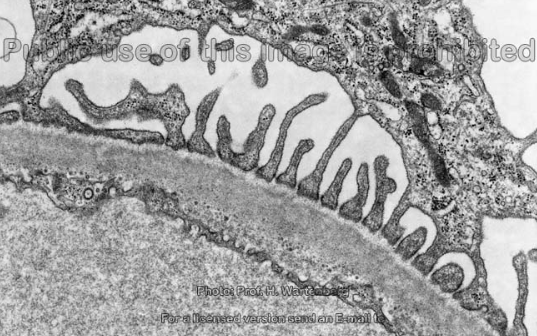

Label this electron microscopy of the glomerulus?

Basement membrane dark as negatively charged so lots of electrons